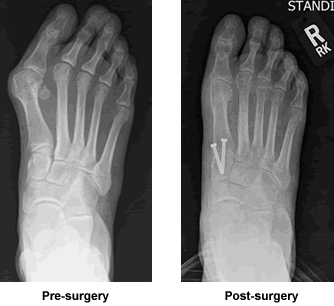

Thank you again Dr. Leavitt for working your gift on my very deformed foot. I wear pretty sandals in the warm weather and can fit into boots and just about any shoe I want to wear with no pain of a bunion. But beyond the aesthetic I have better posture and can feel the change in my body. I feel better about growing older with my foot working as it was meant to. We go to an orthodontist to straighten our teeth, why not go to "Dr. Leavitt" for the healthy feet needed to keep us moving and holding up these bodies. It was a big decision to do such major surgery but I knew I was in good hands and I couldn't be happier. Thank you and my God continue to Bless you.